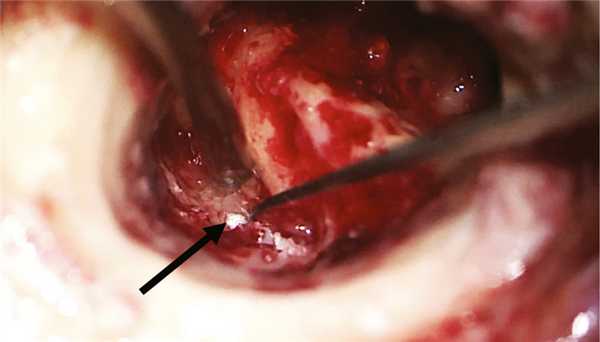

Хирургическое вмешательство было проведено в условиях многокомпонентной анестезии с интубацией трахеи и с применением мониторинга ЛН методом игольчатой электромиографии при непрерывной стимуляции с бормашины. Выполнена инфильтрация мягких тканей заушной области 0,5% раствором наропина 15 мл. Произведен разрез в заушной области справа. Отсепарованы мягкие ткани до кости и кожа задней стенки НСП до фиброзного кольца. Бором снят навес задней стенки НСП и выполнена антротомия. Антрум заполнен грануляционной тканью, блокирующей aditus ad antrum. При проведении тимпанотомии с ревизией барабанной полости отмечено, что рубцово-измененная барабанная перепонка эпидермизирована и спаяна с медиальной стенкой барабанной полости. После удаления патологически измененной барабанной перепонки обнаружены явления метаплазии слизистой оболочки медиальной стенки барабанной полости с развитием грануляционно-фиброзной ткани. Тимпанальное устье слуховой трубы сужено и блокировано полипом. Цепь слуховых косточек сохранена. Молоточек и наковальня удалены. При проведении стимуляционной электромиографии получены М-ответы при пороговой электрической стимуляции в 0,9 мА с горизонтального отдела ЛН, покрытого метаплазированной слизистой оболочкой. Симптом передачи колебаний с подножной пластинки стремени на окно улитки отсутствовал. Бором выполнена радикальная операция. Сформированная трепанационная полость не содержала холестеатомных масс. В полипозно-измененной слизистой оболочке антромастоидальной полости после удаления инфралабиринтных клеток в проекции сагиттального ПК обнаружена холестеатома (рис. 2). Рис. 2. Интраоперационная картина трепанационной полости после выполненной радикальной операции на правом ухе. Стрелкой указана холестеатома в инфралабиринтных клетках височной кости.

Холестеатома заполняла собой все инфралабиринтное пространство с разрушением изнутри сагиттального ПК, преддверия, базального завитка улитки, компримировала твердую мозговую оболочку задней черепной ямки и внутреннюю яремную вену. По ходу распространения эпидермиса удалены сагиттальный ПК с сохранением эндолимфатического протока, ретрофациальные клетки, клетки гипотимпанального клеточного тракта, инфракохлеарные клетки, базальный и апикальный завитки улитки до передней стенки внутреннего слухового прохода. Холестеатома элиминирована вместе с матриксом из инфралабиринтного пространства: с поверхности твердой мозговой оболочки задней черепной ямки, яремной вены, из-под скелетированного фаллопиева канала, из переднего отдела лабиринта, заднего ПК (рис. 3). Рис. 3. Интраоперационная картина инфралабиринтного пространства правой височной кости после удаления холестеатомы.